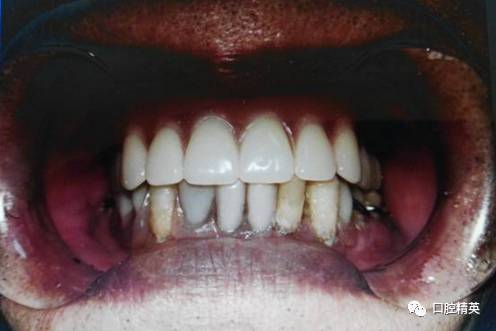

1.面下1/3丰满度良好,鼻唇沟、颏唇沟自然,口角平齐口裂,无下垂。

2.微笑时,上唇下缘露出上前牙切端约2mm。

3.义齿吸附力强,固位良好,张口、说话无脱落。

4.咀嚼食物建议不用前牙切咬,两侧后牙交替咀嚼,义齿无疼痛,固位稳定。